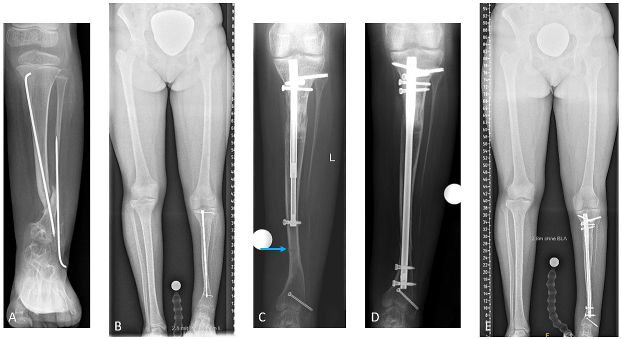

Results: The average number of previous surgeries per patient was six (1–10). The average age at the time of implantation of the lengthening nail was 17 years. Nail insertion was antegrade in three patients and retrograde in two, due to pre-existing ankle arthrodesis. The initial LLD averaged 65 mm (40–90). The average distraction distance was 42 mm (30–50). The average consolidation index (CI) was 36 days/cm (26–55). In one patient with LLD of 80 mm, an initial lengthening of 50 mm was performed. After consolidation of the regenerate, a re-osteotomy and reloading of the nail was conducted for further distraction of 30 mm. In one patient, due to an implant-associated infection, implants were removed nine months postoperatively. In another patient, an atraumatic fracture of the distal tibia occurred ten weeks after the end of distraction, and exchange nailing to a trauma nail was performed. Full bony consolidation was achieved afterward (Figure 1 [Abb. 1]).

Figure 1: A: 6-year-old female with CPT and prior failed surgeries. B: Residual LLD of 5 cm at age 15, after CPT consolidation. C: Fracture T the distal tibia after successful intramedullary lengthening of 4 cm. D: Exchange nailing procedure. E: Intended residual LLD of 1 cm due to ankle fusion; full consolidation of the regenerate bone and fracture site.